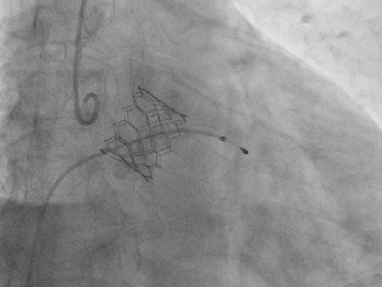

术中关键步骤影像:

25mm球囊预扩

29mm S3瓣膜-3cc释放

瓣膜释放影像